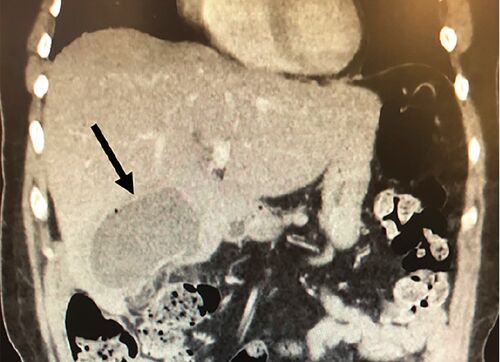

症例44:胆摘後に右季肋部痛を発症した61歳女性(Clin Pract Cases Emerg Med. 2020 Nov;4(4):630-631.)

病歴/身体所見 ・61歳女性 ・数日間持続する右季肋部痛のためER受診 ・受診18日前に急性胆嚢炎に対して腹腔鏡下胆嚢摘出術が実施されている ・バイタルサイン:HR110bpm ・腹部触診で、右季肋部に中等度の圧痛を認める 検査 ・造影CT:辺縁造影効果を伴う7.3…